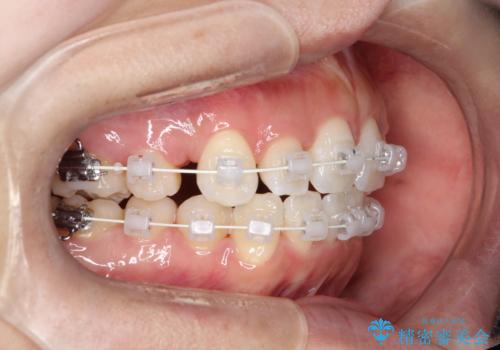

- 矯正装置

- 審美装置

- 前歯の凸凹と口元の突出感を主訴に来院されました。

臼歯関係が上顎前突傾向のため、上の小臼歯を抜歯してワイヤー矯正を行なっております。

下顎の叢生はIPRを行なって配列しています。